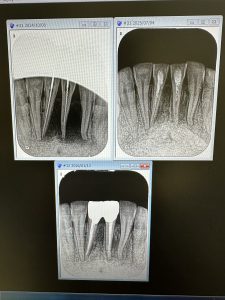

次はフランス人の根管治療後の定期検査

この界隈では珍しい ボンジュール😆